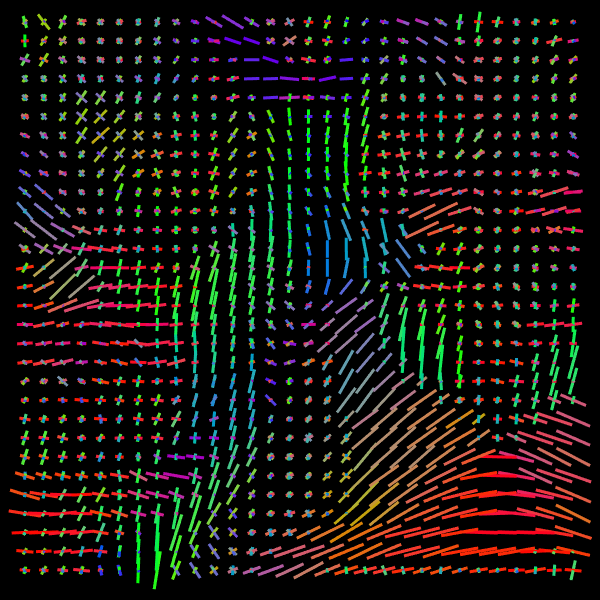

Inference stage. Now we present results of the inference stage with two DW-MRI real datasets. First, the free access dataset Stanford HARDI (Rokem et al., 2015) included in DIPY Library, with dimension (81,106,76) voxels and 160 signals per voxel (number of gradients). The acquisition protocol composed uses 150150150 gradients with b-value equal 200020002000 and 101010 with b-value equal zero. Second, a local DW-MRI with (128,128,70)12812870\left(128,128,70\right) voxels with 646464 gradients with b-value 100010001000 plus 111 gradient with b-value 00, each of them is repeated 555 times resulting in signals of size 325325325. Training time for our models by depends on datasets: The Voxel model takes 1.24sec.1.24𝑠𝑒𝑐1.24sec. for the Stanford HARDI and 1.24sec.1.24𝑠𝑒𝑐1.24sec. for out local dataset. Meanwhile, Neighborhood model takes 1.91sec.1.91𝑠𝑒𝑐1.91sec. for the Stanford HARDI and 3.34sec.3.34𝑠𝑒𝑐3.34sec. for our local dataset. Prediction times are shown in Table 1. Figure 7 compares the final results in a Stanford dataset slice, showing the local detected structure with the studied models. More slices results are presented in Appendix C.

Refer to caption

(c) NNLS

(d) CSD

(e) VOX

(f) NBH

Figure 7: Predicted intravoxel structure in real data with the compared models.